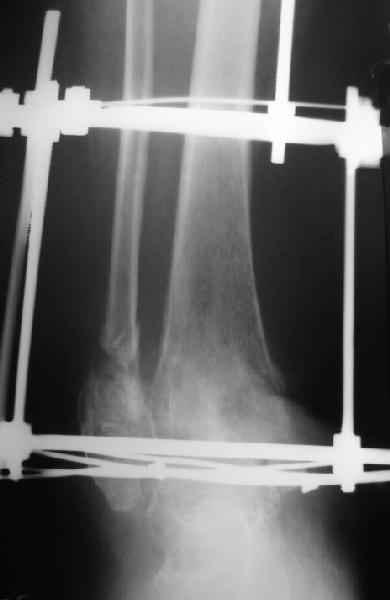

2."Обратите внимание на установку тарана на рентгене! "

В самом деле, снимки некачественные - таран в ротации. Но даже по ним видно, что установка стопы минимум 104 градуса. С одной стороны - В Илизаровской технике пишут, что для женщин допустимо и 110. С другой - почему-то в цивилизованном мире настаивают на четких 90.

А если еще лучше присмотреться, таран в переднем подвывихе, что не кажется допустимым.

Я не совсем понял что за линии на рентгенограмме. Возможно Вы имели в виду это...